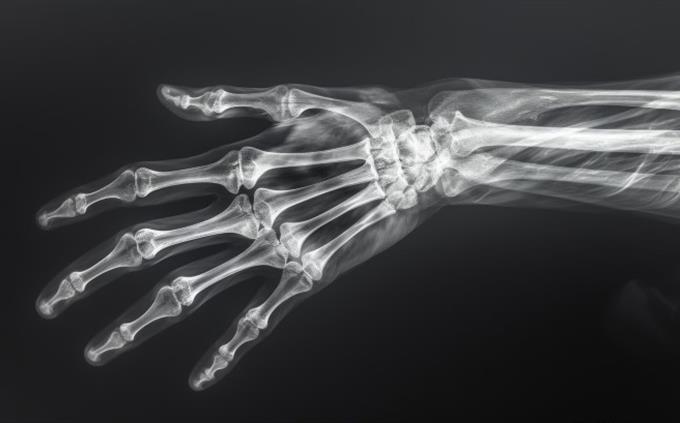

Why can’t X-rays clearly distinguish most soft tissues?

Similar densities absorb X-rays similarly